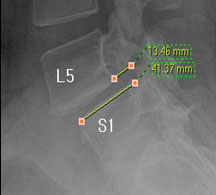

모커리한방병원 표○○ (57, 여) 척추전방전위증 2단계 실제치료사례 이미지

표○○ (57, 여) 척추전방전위증 2단계 입원치료기간 : 20일

입원시 퇴원시

허리 통증지수(NRS) 8 0

엉덩이 통증지수(NRS) 7 0

통증없이 걷는거리(m) 10분

(약 10분 앉은 자세를

유지시 통증 발생)

30분

(약 30분 보행 후 가벼운

통증, 입원 첫날에 비하여

통증 20~30%로 감소)